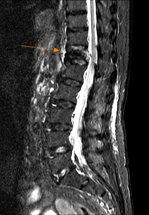

初步檢查後,老太太下肢基本上力量沒有問題,唯一就是在活動的時候,尤其是從床上起身、或是在床上翻身的時候特別疼痛不舒服,咳嗽時也會引發劇烈的疼痛感,細問之下,老太太在意識較不清楚的時候,曾有一兩次跌坐在地上的情況,當下我就大概明白有可能是哪裡發生了問題,在腰椎X光片檢查後,果然發現在胸椎第十二節的地方有一楔形的壓迫性骨折,經磁振造影檢查確定為新生的病灶後,跟家屬解釋目前的情況及可以選擇的治療方式,家屬決定接受椎體成型手術治療,手術過後疼痛馬上緩解,老人家當天下午就能下床自行坐著進食,能再次自行坐著進食,不管是病人或是家屬都對治療的效果感到非常的滿意。

利用磁振造影確定無神經壓迫及病灶發生時間。 |